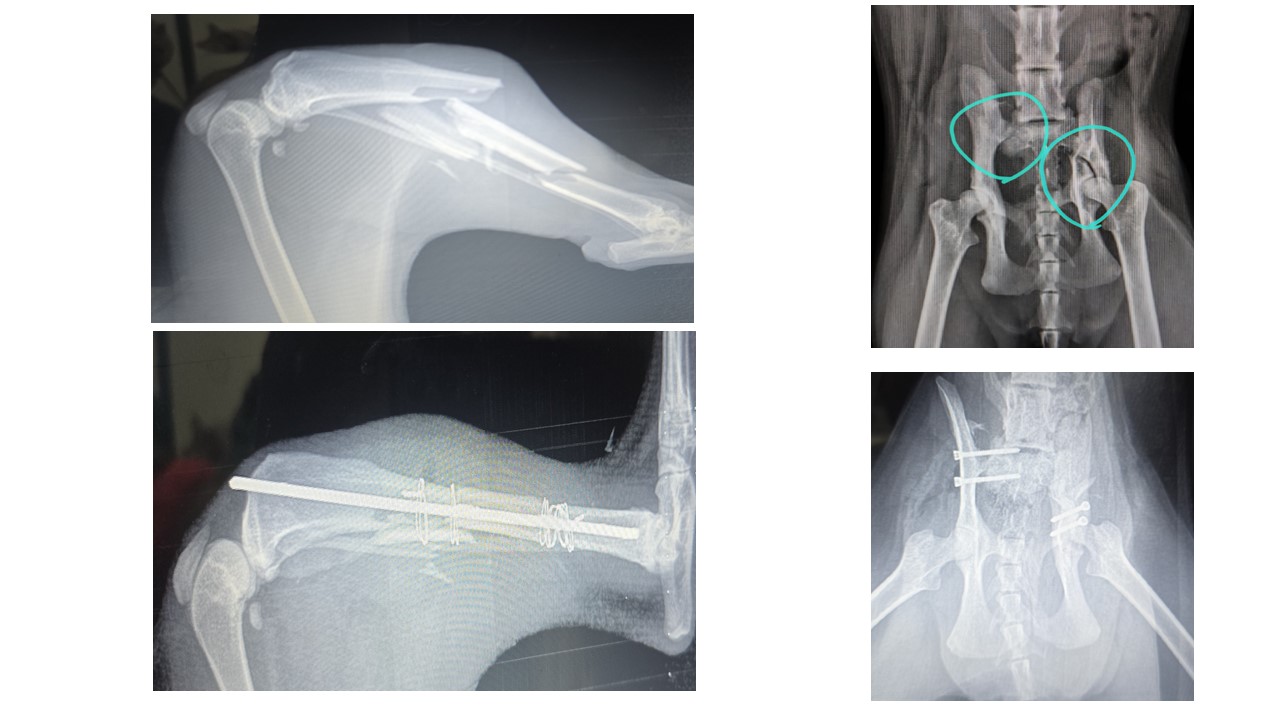

Kliniğimizde, ortopedi alanında uzman hekimimiz eşliğinde birçok operasyon başarıyla gerçekleştirilmektedir. Ortopedik hastalıklarda doğru tanı büyük önem taşır. Bu nedenle, kliniğimize başvuran her hastanın ortopedik şikayetleri, özel uzmanlık alanı cerrahi ve ortopedi olan Op. Uzman Veteriner Hekim Mehmet TABUR tarafından değerlendirilir. Hastanın ihtiyaçlarına en uygun tedavi veya operasyon planı titizlikle oluşturulur. Kliniğimizde tüm ortopedik operasyonlar rutin olarak uygulanmakta ve her işlemde yüksek hijyen ve dikkat standartları korunmaktadır.

Uygulanan Ortopedik Operasyonlardan Bazıları:

• Kalça çıkığı (Luxatio Femoris)

• Ortopedik plak teknolojisi (İnternal fiksasyon plakları)

• Çapraz bağ kopuğu tedavisi

• Dirsek çıkığı (Luxatio Cubiti)

• Patella çıkığı (Luxatio Patella)

• Kas ve tendon yaralanmaları

• Eksternal fiksasyon ile kırık tedavisi

• Atel ile fiksasyon uygulamaları

• Intrameduller pin ile kırık tedavisi

• Omuz çıkığı

• Sakroiliak ayrılma

Her vakada hasta konforu ve uzun vadeli sağlığı ön planda tutulur. Operasyon sonrası iyileşme süreci de veteriner hekimlerimiz tarafından yakından takip edilmektedir.